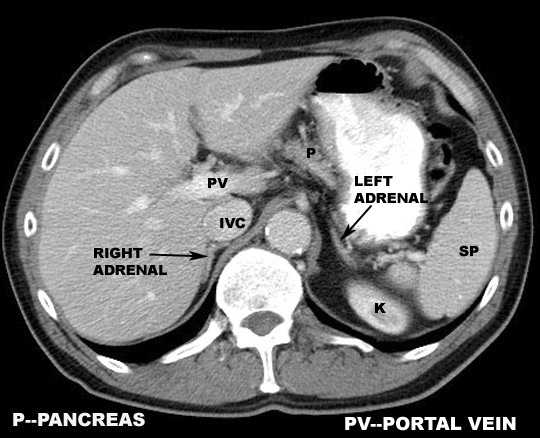

Portal Vein. Click the image for labeling.